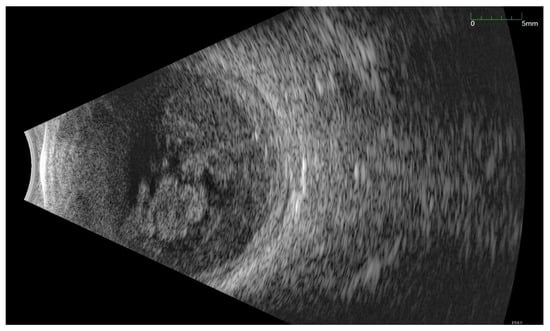

All of the above circumstances make the assessment of the vitreous body and retina in an ophthalmoscopic examination often impossible. The basic diagnostic tool in such cases is an ultrasound examination. Vitritis is inherent part of EE. Ultrasonography is nonspecific, however, it can indicate severity of the posterior involvement (Figure 6 and Figure 7) [80]. It also allows the assessment of the progression of changes (Figure 8). Features characteristic for EE include strands and membranes with reduced mobility (Figure 9). Other common changes are retinal detachment and subretinal abscess (Figure 10).

Figure 10.

Ultrasound B scan with numerous hyperechoic densities in vitreous chamber. The blue arrow marks a detached retina. Hyperechoic masses are visible under the retina.